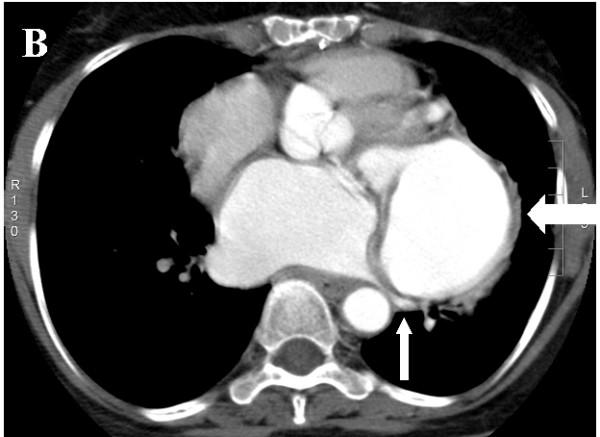

Subannular left ventricular pseudoaneurysm following mitral valve replacement.

Delayed development of left ventricular pseudoaneurysm is a rare late complication of mitral valve prosthesis and requires early surgical intervention. Here we describe the occurrence of such a complication diagnosed 6-months after the valve surgery in a 60-year-old lady. The anatomic delineation of subannular left ventricular pseudoaneurysm using multiple imaging modalities including CT angiography is also being discussed.